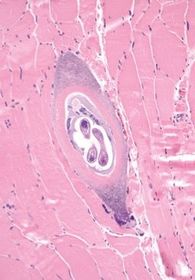

| Trichinella spiralis Epidem. | Worldwide, including US Associated with pork consumption (haram!) |

| Trichinella spiralis Life Cycle | *Pigs contain adult worms & encysted larvae *Humans ingest encysted larvae in undercooked meat *Larvae develop into adults in small intestine *After mating, females release larvae *The released larvae get into blood stream and lodge in muscle *Can get cardiac, CNS, lung involvement |

| Trichinella spiralis Clinical Man. | Periorbital & facial edema, conjunctivitis Fevers, myalgias & weakness Rarely myocarditis, CNS involvement & pneumonitis Eosinophilia |

| Trichinella spiralis Treatment | Albendazole |

| Trichinella Spiralis |